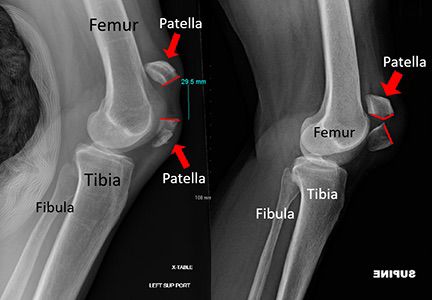

2. Fractures Involving the Joint Surface

Fractures like tibial plateau fractures directly affect the knee joint. Even a small misalignment can lead to arthritis later. Robotic assistance ensures near-perfect joint restoration.

Robotic assisted knee surgery procedure image 2 Robotic assisted knee surgery procedure image 3 Robotic assisted knee surgery procedure image 4 Robotic assisted knee surgery procedure image 5